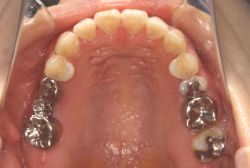

「左奥歯でものが噛めない」という主訴で来院したケースです。診断の結果、基本的には「叢生」という隙間が足りないと言うことが原因の凸凹症例でしたが、左下の乳歯が高校生になってもまだ残存している状態で、そのせいで噛み合わせが極端に悪くなっていました。

検査の結果、乳歯の下には後継ぎの永久歯が先天的に欠如していました。配列の凸凹が厳しく非抜歯で矯正することは難しく、仮に無理をして非抜歯治療をしても後々「後戻り」が懸念されることから、このような症例の場合は通常、上下顎左右第一小臼歯を抜歯させていただくのですが、左下は乳歯を抜歯して、第一小臼歯は残すことにしました。これで結果として、小臼歯部を上下左右で一つずつ減らしたのと同じ状況になります。治療後は歯並びが綺麗になっただけでなく、噛み合わせ的にも正しい状態が確立しています。

このように、先天的に永久歯が足りないという症例は最近増えています。親知らずはなくても特に問題になりませんが、その他の歯が足りないと言うのは審美的にも機能的にも重大な障害となります。しかし、矯正治療を正しく行えば、結果として歯がすべてあった場合と全く同じ仕上げにすることも可能です。